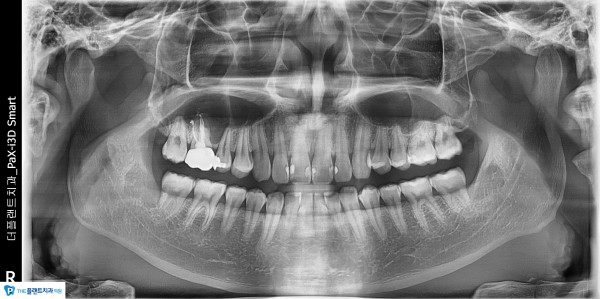

●치료명 : 매복 사랑니 발거

●치료 내용 : #38,48 국소마취후에 발거